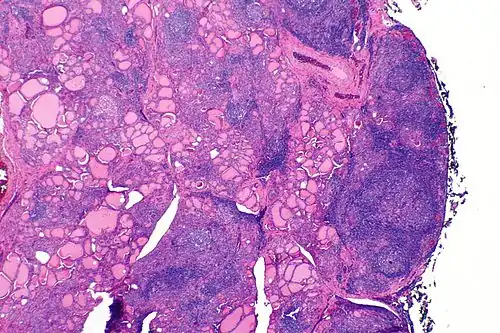

| A micrograph of the thyroid of someone with Hashimoto's thyroiditis | |

Microscopic examination (histology) will show lymphocytes (including plasma B-cells) diffusely infiltrating the parenchyma.[55] The lymphocytes are predominately T-lymphocytes with a representation of both CD4+ and CD8+ cells.[5] The plasma cells are polyclonal, with present germinal centers resembling the structure of a lymph node[5] (also called secondary lymphoid follicles, not to be confused with the normally present colloid-filled follicles that constitute the thyroid).[55]

In late stages of the disease, the thyroid may be atrophic.[10] Colloid-filled follicles shrink, and the cuboidal cells that usually line the follicles become Hürthle cells.[5] Fibrous tissue may be found throughout the affected thyroid as well.[5] Severe thyroid atrophy presents often with denser fibrotic bands of collagen that remain within the confines of the thyroid capsule.[55]

Generally, pathological findings of the thyroid are related to the amount of remaining thyroid function — the more infiltration and fibrosis, the less likely a patient will have normal thyroid function.[5] A rare but serious complication is thyroid lymphoma, generally the B-cell type, non-Hodgkin lymphoma.[24]